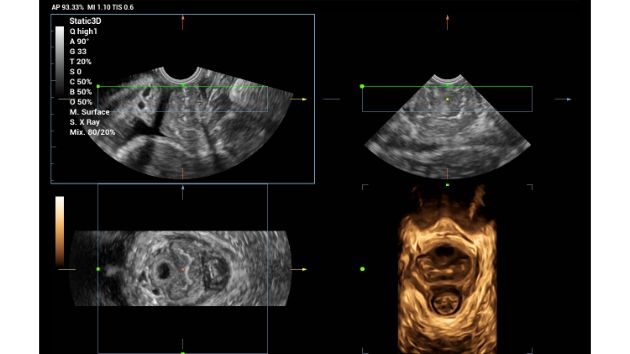

Smart CNS+Meas

Smart Pelvic 3D

Smart Spine 3D